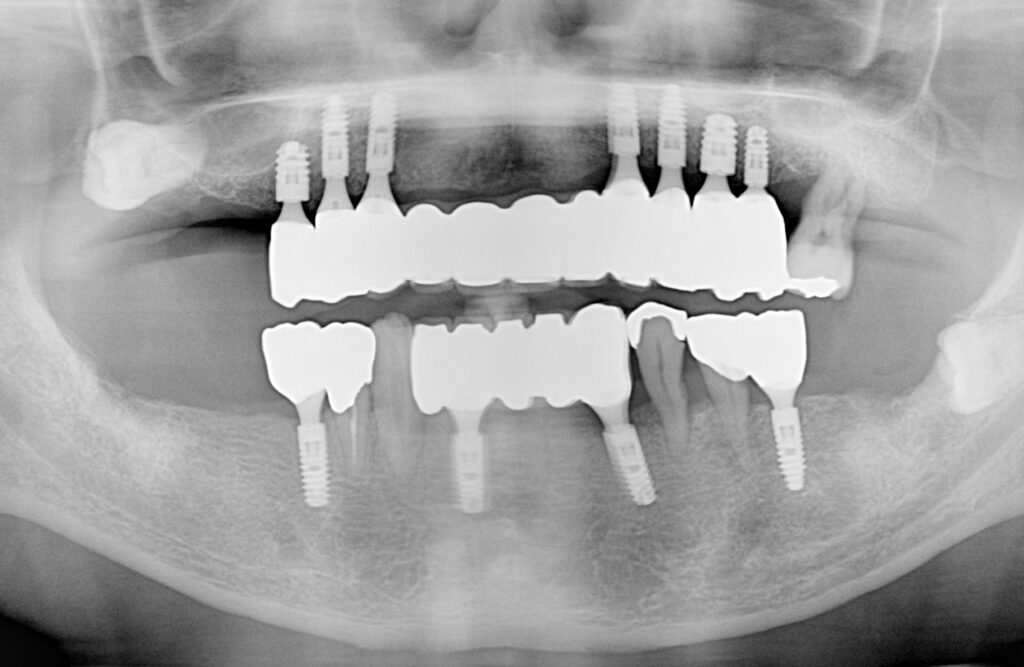

60歳代男性。上顎のぐらぐらした歯を抜いて、部分入れ歯となりました。固定性のインプラント治療を選んで頂き、時間をかけて治療をさせてもらいました。歯を喪失しただけでなく、歯周病で歯ぐきもやせてしまったので、やせたしまった分の歯ぐきもピンクセラミックで修復し、11本連結のインプラントブリッジとしました。『インプラント治療には最初に費用がかかるが、長期的に見れば、入れ歯の煩わしさやブリッジで健康な歯を削る損失を補ってあまりある恩恵がある』とのことです。この患者さんのように、適切なメンテナンスを続けることで、長期的な機能回復が期待できます。当クリニックのインプラント治療で、友人との食事を心から楽しめるようになります。食事を楽しむための特別な治療法を複数用意しておりますので、あなたに合った治療法を一緒に見つけ、ご家族や友人との食事を大いに楽しみましょう!(※下の歯は上顎の治療の終了後、インプラント治療をしてあります。)

上顎の部分入歯をやめて、固定性のインプラント治療をし、12年経過した症例